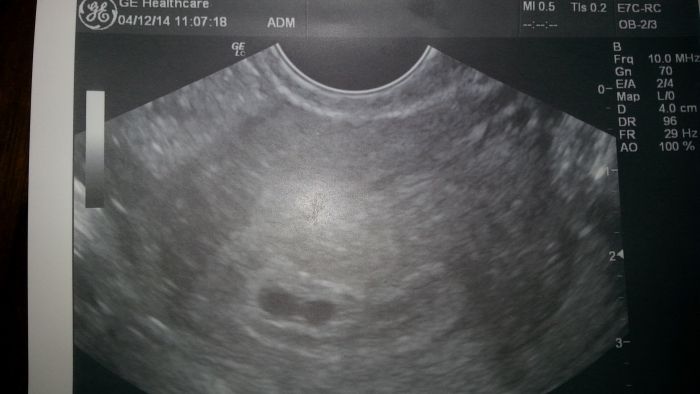

Dobrý den.. podle menstruace jsem v 8tt. Čekáme dvojčátka jenže na ultrazvuku nebylo vidět ani jedno srdičko jsou rozdílné váčky.. mam strach, těšíme se na obě.. nemá někdo podobne problémy?

[680465] Tyy jo to je pupik...a kolikaty tyden je na fotce?

Na fotce je 6 týden